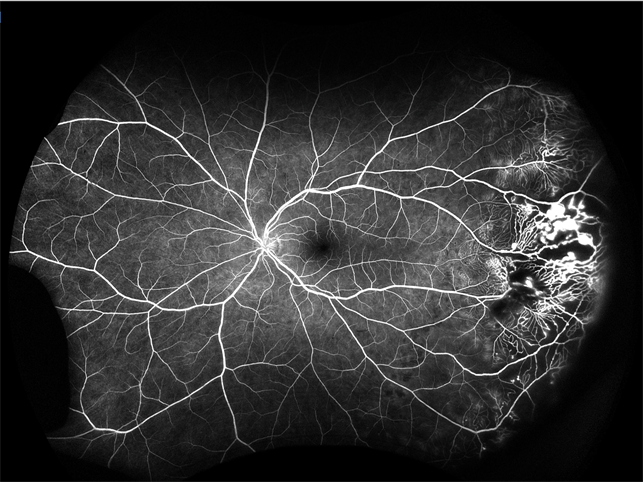

Coats' disease. Angiography widefield imagebank

Angiography widefield imagebank. Coats' disease. Optos california fa ultra-widefield retinal imaging systems